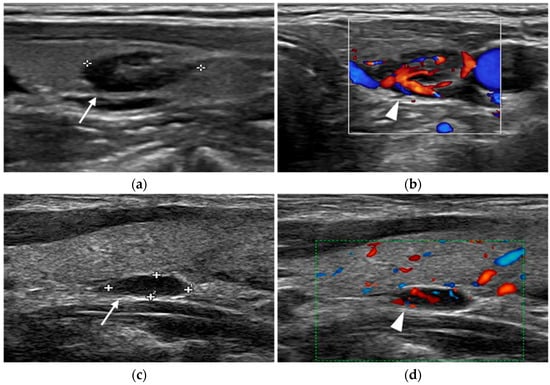

Ultrasound

- Rickes, S.; Sitzy, J.; Neye, H.; Ocran, K.W.; Wermke, W. High-resolution Ultrasound in Combination with Colour-Doppler Sonography for Preoperative Localization of Parathyroid Adenomas in Patients with Primary Hyperparathyroidism. Ultraschall Med. 2003, 24, 85–89. [Google Scholar] [CrossRef] [PubMed]

- Lane, M.J.; Desser, T.S.; Weigler, R.J.; Jeffrey, R.B., Jr. Use of color and power Doppler sonography to identify feeding arteries associated with parathyroid adenomas. Am. J. Roentgenol. 1998, 171, 819–823. [Google Scholar] [CrossRef]